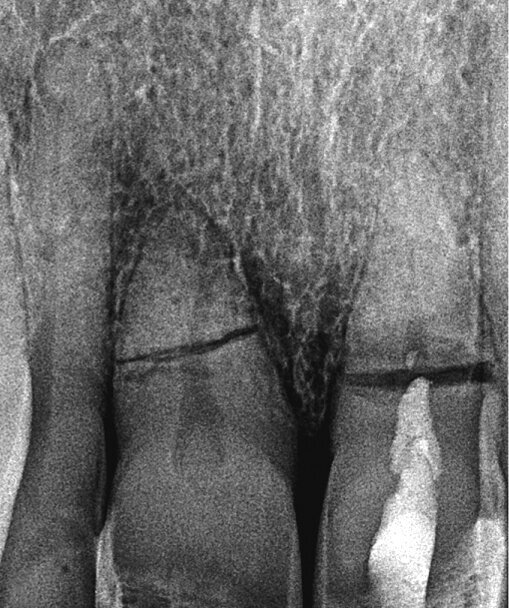

Pacijent u dobi od 66 godina doživio je traumu s posljedičnom frakturom korijena i palatinalnom dislokacijom zubi 11 i 21. Zubi su u okviru hitnog zbrinjavanja reponirani i splintirani (Slika 1.). Na pojedinačnoj rendgenskoj snimci zubi 11 i 21 uočava se intraalveolarni poprečni lom (Slika 2.). Prema aktualnim smjernicama takav lom u početku ne zahtijeva endodontsko liječenje ako se može isključiti da frakturna linija preko gingivnog sulkusa, odnosno parodontne pukotine komunicira s usnom šupljinom.

Slika 2. Početna situacija: Pojedinačne snimke zubi 11 i 21 s jasno vidljivim lomom korijena